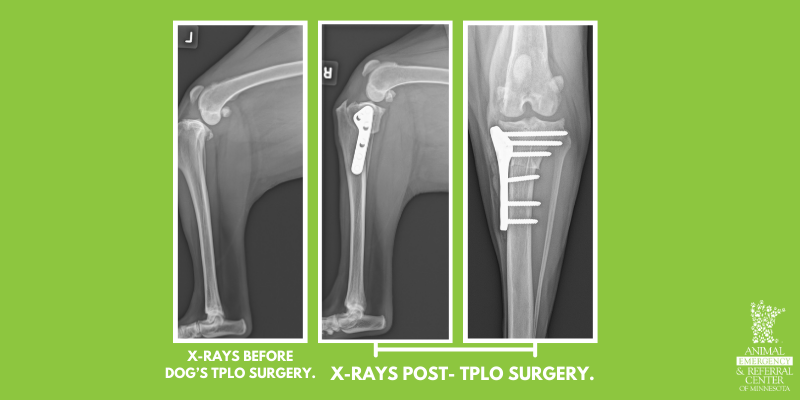

- The procedure typically performed at AERC for a CCL injury is a Tibial Plateau Leveling Osteotomy (TPLO).

- The surgeon makes a cut in the shin bone (tibia), rotates it, and stabilizes the new position with a bone plate and screws. This alters the biomechanics of the knee so that the limb can be functional without the CCL.

- Recheck radiographs are performed 8 weeks after surgery to ensure the bone is healing well before returning to normal activity.